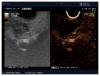

Contrast agents are increasingly being used to characterize the vasculature in an organ of interest, to better delineate benign from malignant pathology and to aid in staging and directing therapeutic procedures. We review the mechanisms of action of first, second and third generation contrast agents and their use in various endoscopic procedures in the gastrointestinal tract. Various applications of contrast-enhanced endoscopic ultrasonography include differentiating benign from malignant mediastinal lymphadenopathy, assessment of depth of invasion of esophageal, gastric and gall bladder cancers and visualization of the portal venous system and esophageal varices. In addition, contrast agents can be used to differentiate pancreatic lesions. The use of color Doppler further increases the ability to diagnose and differentiate various pancreatic malignancies. The sensitivity of power Doppler sonography to depict tumor neovascularization can be increased by contrast agents. Contrast-enhanced harmonic imaging is a useful aid in identifying the tumor vasculature and studying pancreatic microperfusion. In the future, these techniques could potentially be used to quantify tumor perfusion, to assess and monitor the efficacy of antiangiogenic agents, to assist targeted drug delivery and allow molecular imaging.